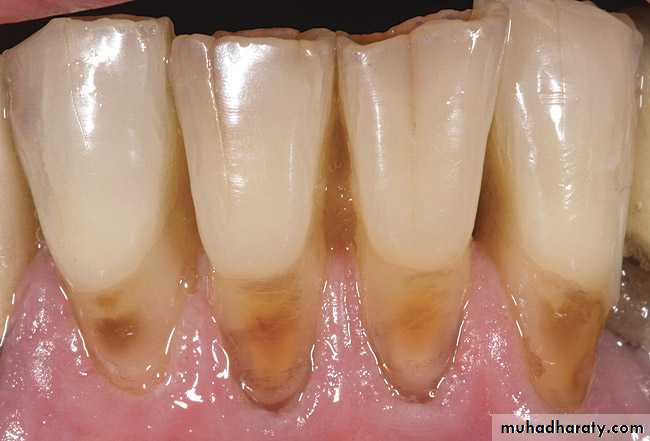

According to severity it is classified in to:Grade 1: is characterized by an incipient lesion , the surface texture is soft and irregular and can be penetrated with a dental explorer, there is no surface defect and pigmentation variable light tan to brown.

Grade 2: is characterized by a shallow lesion, the surface texture is soft, irregular and rough and can be penetrated with a dental explorer, there is surface defect (less than 0.5 mm in depth) and pigmentation variable from light tan to dark brown.Root surface caries severity IndexBilling et al 1985

Grade3:is characterized by cavitation of the surface texture which is soft and can be penetrated with a dental explorer. There is a penetrating lesion and cavitation is present (greater than 0.5 mm in depth) however there is no pulp involvement, pigmentation is variable ranging from light brown to dark brown.

Grade4:is characterized by pulpal involvement, there is a deeply penetrating lesion pulpal or root canal involvement, pigmentation is variable ranging from brown to dark brown.